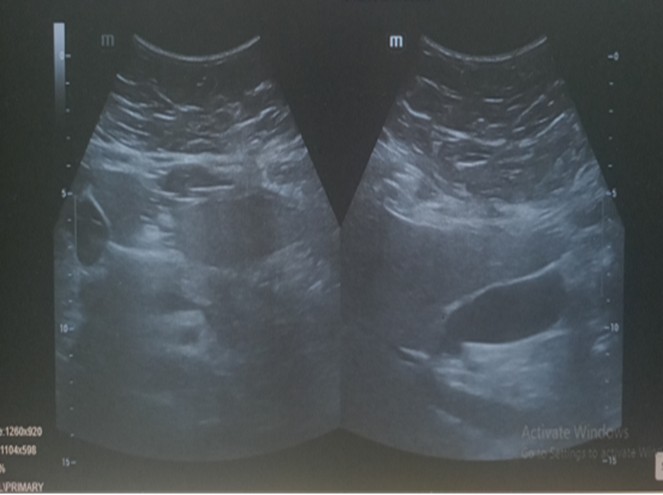

Due to her progressively worsening obesity and its impact on her daily life, she was admitted for an elective laparoscopic sleeve gastrectomy. The surgical procedure was performed successfully without any intraoperative complications, and a drain tube was placed to monitor postoperative output. Her immediate postoperative recovery was uneventful. She tolerated the prescribed diet progression, had stable vital signs, and her pain was well controlled. She was discharged on the 6th postoperative day in good condition with appropriate postoperative instructions. On the 13th day after discharge, the patient returned with complaints of severe abdominal pain. A CT scan of the abdomen and an abdominal ultrasound were performed to rule out postoperative complications such as gastric leak or intra-abdominal collection. Both imaging studies showed no evidence leak or abnormal findings.

USG: Moderate hepatomegaly. No free fluid in the abdomen

Fig (2): USG Abdomen